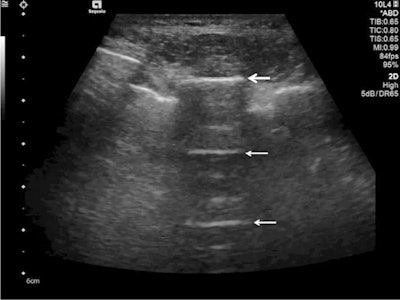

Follow-up of an intensive care unit patient with COVID-19 pneumonia after mechanical ventilation. An indirect sign of recovery is the appearance of A-lines (white arrows) through the recovery phase. No major pleural fragmentation (bold white arrow) is seen, but a mirror effect is visible (left white arrow). All figures courtesy of Dr. Dirk-André Clevert and colleagues and Insights into Imaging.Lung ultrasound in experienced hands can give results that are comparable to chest CT and even superior to standard chest radiography for assessment of pneumonia and/or adult respiratory distress syndrome (ARDS), they explained.

A-lines are reverberation artifacts triggered by oscillating tissue with an air interface, causing the ultrasound waves to be reflected strongly and to reverberate. Among the probe and lung surface, the ultrasound waves bounce back and forth. A-lines are parallel horizontal repetition lines of the pleural surface, appearing deeper on the display screen.

Ultrasound detected A-lines using an abdominal probe. A-lines (white arrows) appear as bright horizontal lines deep to the pleural line (bold white arrow).Due to the fact that this is a classic reverberation artefact, the distance from the skin to the pleural surface equals the distance from the pleural line to the first A-line, the first A-line to the second A-line, etc. The A-profile is shaped by intact ("dry") lung parenchyma containing air when it is combined with normal lung sliding. If sliding is absent, it is intensely suggestive of a pneumothorax.